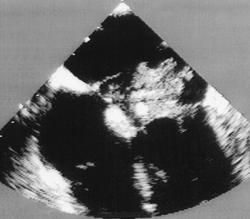

Метод эхокардиографии позволяет верифицировать диагноз. Опухоль левого предсердия вызывает появление «облачка» эхо-сигнала между створками митрального клапана во время диастолы желудочков, во время систолы он виден в полости левого предсердия. При линейном сканировании на протяжении сердечного цикла можно проследить за движением «облачка» из левого предсердия в левый желудочек и обратно. Опухоль искажает характер кривой движения передней створки митрального клапана, вызывая деформацию диастолического движения, и приводит к смещению этой створки к межжелудочковой перегородке. Плотная гладкая капсула миксомы дает четкие контуры отраженного эхо-сигнала, тогда как опухолевые массы без оболочки имеют смазанный контур. При двухмерной эхокардиографии миксо-ма видна в полостях сердца в виде более светлого образования на темном фоне, движение опухоли визуализируется на протяжении всего сердечного цикла.

Миксома сердца - первичная внутриполостная гистологически доброкачественная опухоль, встречается в любом возрасте, наиболее часто в 30-60 лет, у женщин в 2-4 раза чаще, чем у мужчин (рис. 61). Миксома наиболее часто локализуется в полости левого (75% ) или правого (20%) предсердия (рис. 62), крайне редко - в желудочках сердца (рис. 63).

Патологическая анатомия. Миксома представляет собой солитарное, реже множественное новообразование округлой или овальной формы, не распространяющееся далее субэндокардиальных слоев сердца. Макроскопически миксомы имеют две разновидности: первая - полупрозрачная, бесцветнаяжелатинозная по консистенции, фиксированная к стенке сердца более или менее широким основанием; вторая - округлая плотная масса, свисающая на ножке (80%). Внешний вид опухоли напоминает полип или виноградную гроздь диаметром от 5 мм до 8 -12 см с крупно-или мелкозернистой поверхностью, масса ее может достигать 250 г. Поверхность опухоли блестящая, капсула отчетливо выражена. Цвет может Рис. 61. Первичные опухоли сердца (по F. Netter, 1969, с изменениями) Рис. 62. ЭхоКГ миксомы правого предсердия (В-режим) варьировать от зеленовато-серого до желтовато-коричневого, опухоль желеобразной или значительно реже эластической консистенции. В самой опухоли могут обнаруживаться дистрофические изменения - некрозы , кровоизлияния, реже происходит обызвествление.